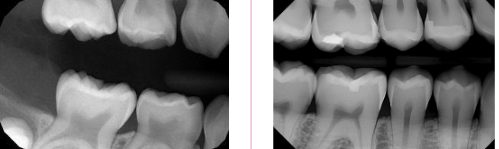

<p><span><strong>How to use the differences in identifying the dentition in </strong></span><strong>radiographs: start with the roots&nbsp;</strong></p>

How to use the differences in identifying the dentition in radiographs: start with the roots

knowt flashcard image

<p><span><strong>How to use the differences in identifying the dentition in </strong></span><strong>radiographs: look at the pulp</strong></p>

How to use the differences in identifying the dentition in radiographs: look at the pulp

Key differences to identify primary vs permanent dentition

 Enamel and dentin are thinner in primary

 Pulp chamber is wider

 Pulp horn is more prominent

 Smaller root trunk for primary

<p><span><strong> Enamel and dentin are thinner in primary </strong></span></p><p><span><strong> Pulp chamber is wider </strong></span></p><p><span><strong> Pulp horn is more prominent </strong></span></p><p><span><strong> Smaller root trunk for primary</strong></span></p>